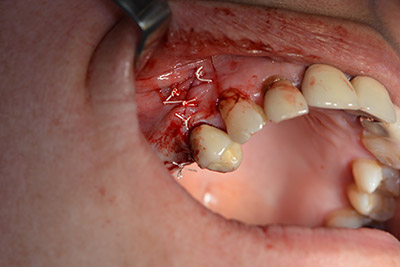

An absorbable membrane was used as the barrier in the buccal direction and covered the augmentation. Finally, saliva-proof sutures were placed (Fig. 15 to 19).

saliva-proof wound closure

Image 19